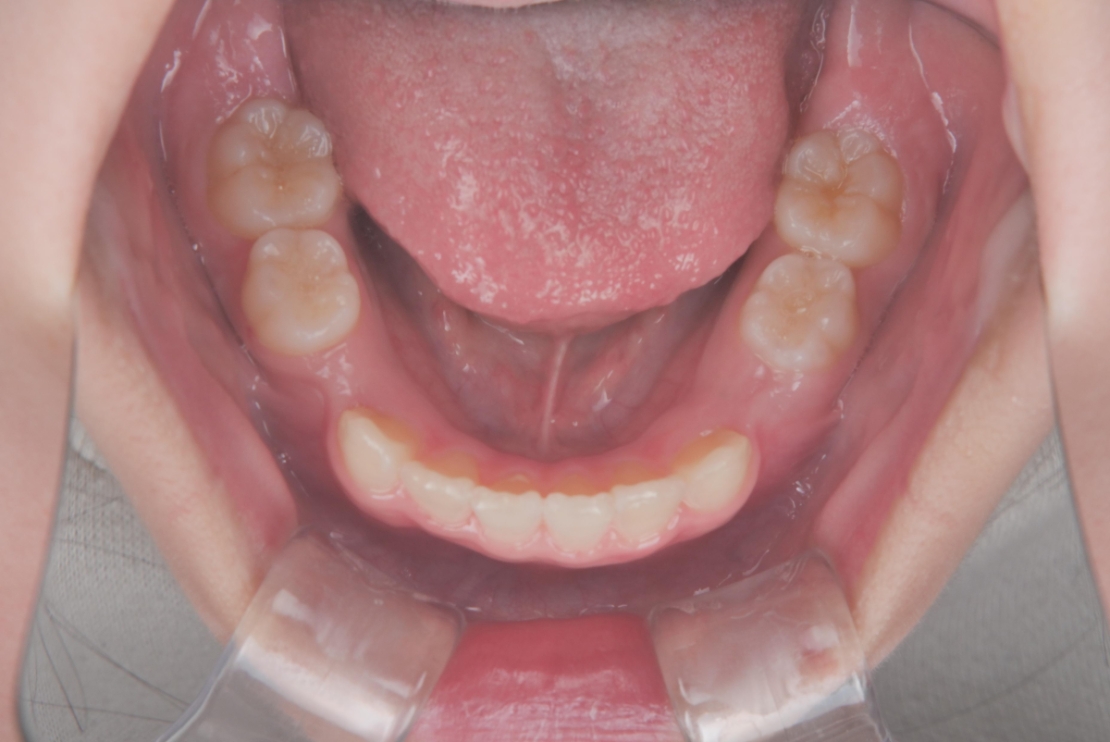

AFTER

治療は、マウスピース矯正インビザライン・ファーストにて矯正治療を行い、成長を活かしながら歯列を整えていきました。治療期間はわずか11ヶ月で完了し、ガタつきと歯の傾きは改善しています。

スタート時8歳の女の子の症例です。主訴は歯並びのガタつきと、上の2番目の歯が八重歯のようにハの字に傾いていることでした。